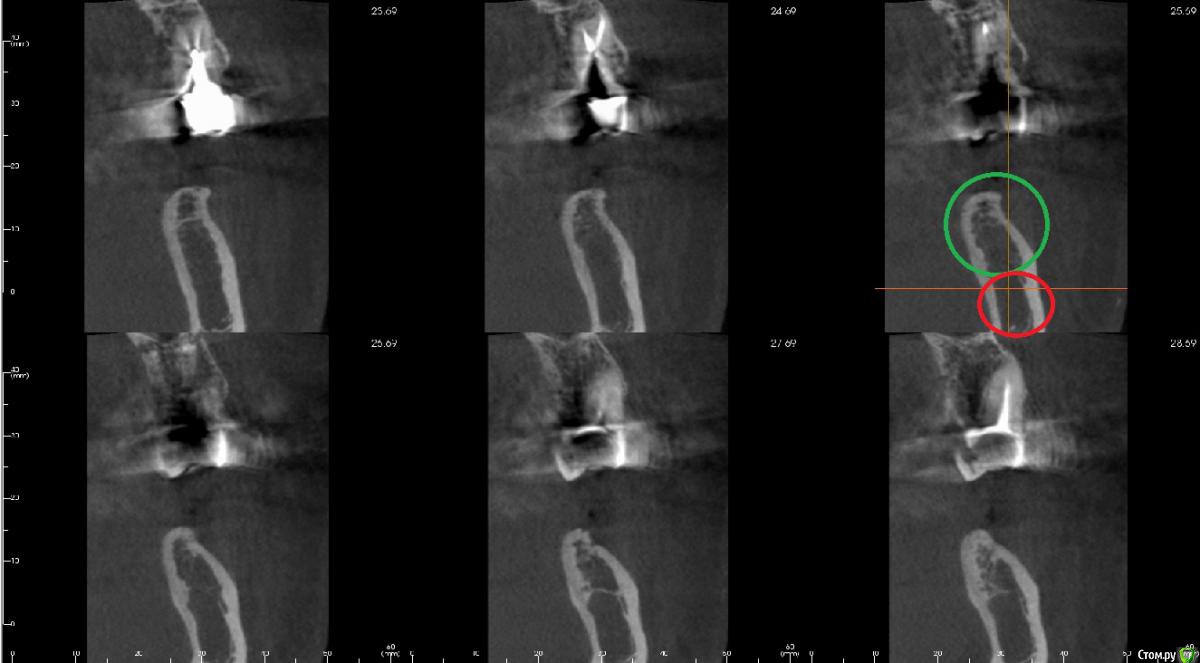

kamranchick Опубликовано 29 марта, 2017 Поделиться Опубликовано 29 марта, 2017 Мой молодой взгляд видит такую картину) 1 Ссылка на комментарий

Irouil Опубликовано 29 марта, 2017 Поделиться Опубликовано 29 марта, 2017 На первом срезе (левый верхний) я на 99% уверен что канал видно - слишком уж правильный контур. Плюс я бы, конечно, все таки с мезио-дистального среза пошел, как и Антон советовал - имея первую реперную точку на вестибуло-оральном срезе и отстреливаясь выше нижней стенки можно построить пусть и не идеально, но примерно канал Ссылка на комментарий

bullbull Опубликовано 30 марта, 2017 Автор Поделиться Опубликовано 30 марта, 2017 Я при повторном осмотре выставил примерно так. Может перестраховка. Но 4.0.10 становятся неплохо.Такая низкая плотность не является патологией? Ссылка на комментарий